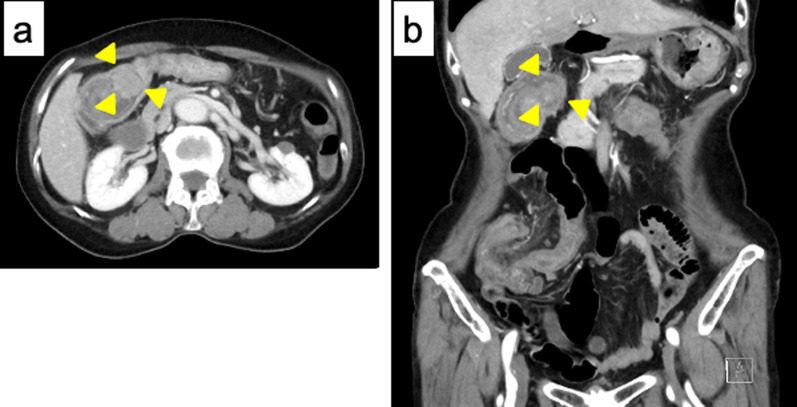

A 72-year old woman presented with a 10-day history of vomiting, diarrhea, and abdominal pain. She had no relevant medical history and no family history of malignancy. Physical examination showed a mass over the right abdominal region, but palpation elicited no significant abdominal tenderness. Laboratory tests were within normal ranges, except for a slightly increased level of C-reactive protein (0.70 mg/dL). Abdominal contrast-enhanced computed tomography (CT) showed the target sign in the ascending colon. An enhanced nodule was detected at the lead point, suggesting the presence of a tumor (Fig. 1a, b). Colonoscopy showed a tumor at the lead point of the intestinal intussusception (Fig. 2a). Evidence of bowel wall edema and bowel obstruction was also seen (Fig. 2b). Biopsy revealed the tumor as a neoplastic lesion, suspected as NET. Immunohistochemical findings showed the tumor cells were positive for chromogranin A, synaptophysin, and CD56. The impression was NET G1.

Fig. 1.

An abdominal contrast CT scan. Target sign is detected in the ascending colon in right upper abdomen, which indicates intussusception. a Axial views. b coronal views. Arrowhead: a lead point